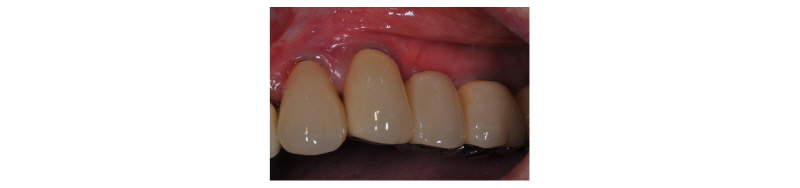

Fig. 16. Clinical clinical view. Final prosthesis. |

Dong- Wook Chang : The Application of Ridge Splitting Procedure in Severely Atrophied Maxillary Alveolar Ridge: Case Reports. Implantology 2017 |